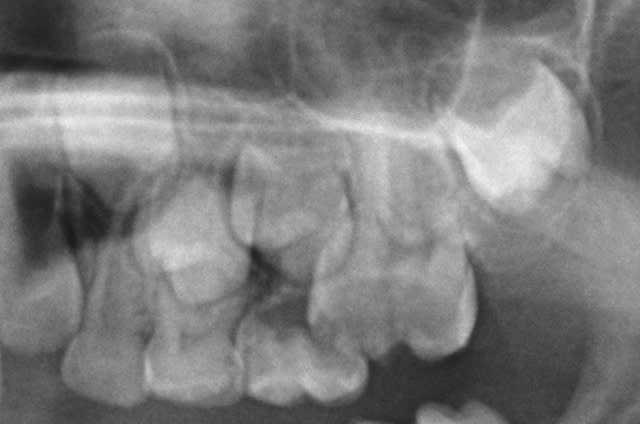

Qui ferait quoi dans le cas ci-dessous : 11 ans, patient en classe I, normodivergent, hygiène médiocre, très coopérant au fauteuil. 36 présente une carie similaire en lingual. Ces deux dents sont vitales.

De plus, les 5 peuvent aussi rester bloquées par la bascule des 4 et 7... vu la pano... et les germes des 8 ont l'air pas mal...